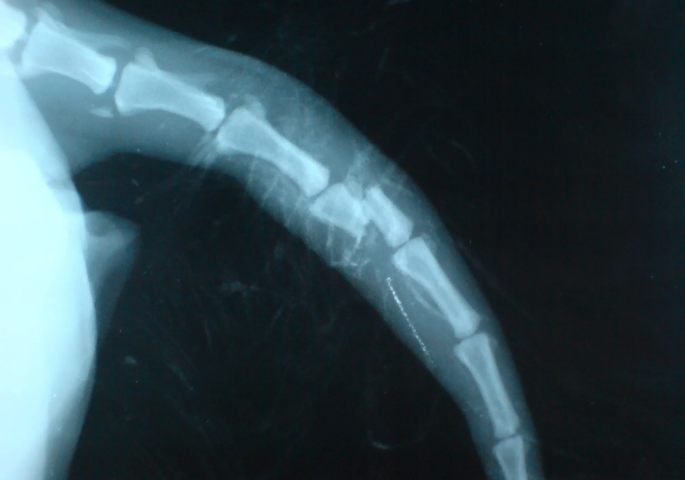

При подозрении на перелом или вывих нужно показать собаку ветеринару, сделать рентген и после этого уже получить лечение. И помните, чем раньше вы начнете лечение, тем лучше будет результат. Не затягивайте с посещением клиники, иначе ваш питомец может лишиться столь важного органа, как хвост.